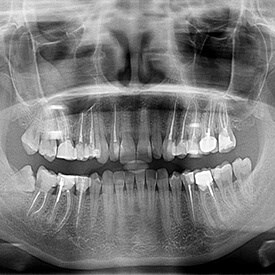

- Digital X-Rays Service

Digital x-rays are a type of advanced technology offered at our office that allows our team to look for a number of underlying concerns, like decay.